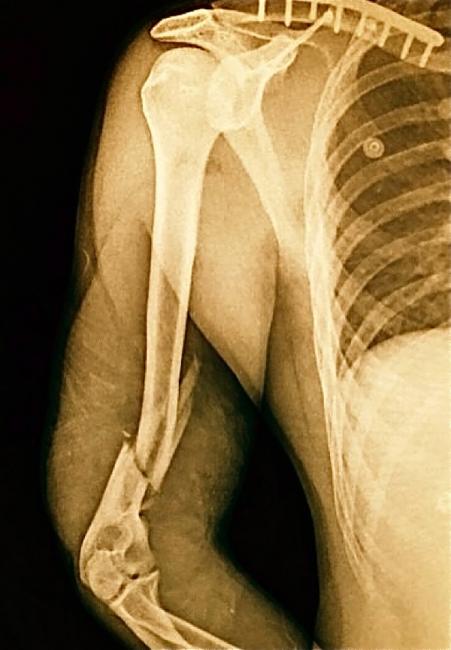

PING: After watching Trey Canard and Jake Weimer go down last weekend it got me thinking back to the many times I had to dig out of that hole when I was racing. Of course there is the physical pain that goes along with being assaulted by your bike and/or the ground, but there is also very real psychological and emotional struggles involved, and often times those hurt the worst. The last big one I had was when I had a comfortable lead in the AMA Supermoto series and crashed while leading a main event in Oregon. I snapped both bones in my arm, and as I stood up I had to grab my arm to keep it from drooping lifelessly toward the ground. All I could think about was a title that was slipping away. The pain was legit but it didn’t hurt as bad as seeing that number one plate go away.

This isn’t the first rodeo for Trey or Jake, though. In fact, if we are going with the cowboy analogy, Trey is the grizzled, Copenhagen-spitting, bowlegged, ten-gallon-hat-wearing bronc-buster of motocross injuries. Surgery is never fun but knowing that you are going to lose all your fitness is frustrating. On top of that you have the residual effects of whatever body part you smashed up, the time off the bike, the time away from racing, and your stock in the industry that has surely dropped from being injured. It's a long road back physically, but most riders enjoy hard work. You have to keep a positive attitude and try to make gains every day when you get out of bed (Trey has proven to be exceptionally sharp here). And you have to be able to line back up when the time comes up push the crashes, pain, surgery, and fear out of your head and do your job. When you are no longer able to do that it’s time to look for something else to do. This is the most brutal aspect of our sport, and I wish Trey and Jake the best of luck on their latest trek back up the mountain.

There's one points fight that's worth watching, though. With second-place Trey Canard sadly now out of 450SX with a broken arm, Eli Tomac is likely to take over second. The current battle between Cole Seely and Chad Reed for fourth could become a fight for third. (Reed, fifth in points, would have to collect 34 points in five weeks to jump Canard. Seely is 10 points ahead of Reed, so he needs 24 to get past Trey.)